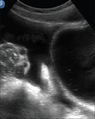

Abnormal